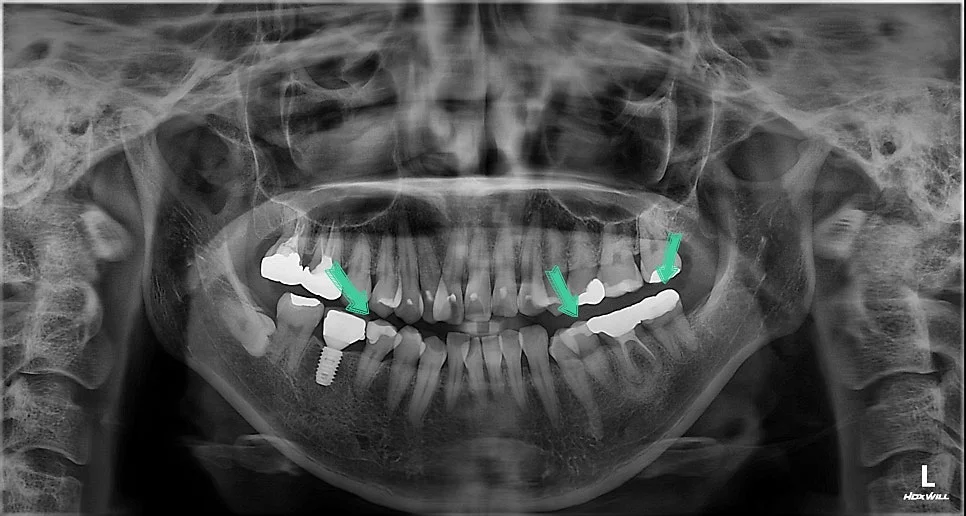

파노라마 방사선 사진 — 파란색 화살표로 치료 대상 부위 종합 표시

파노라마 사진상에서는 다음과 같이 관찰되고 다음과 같이 치료 계획을 세웁니다!

파노라마 사진 — 치료 계획을 화살표로 종합 표시